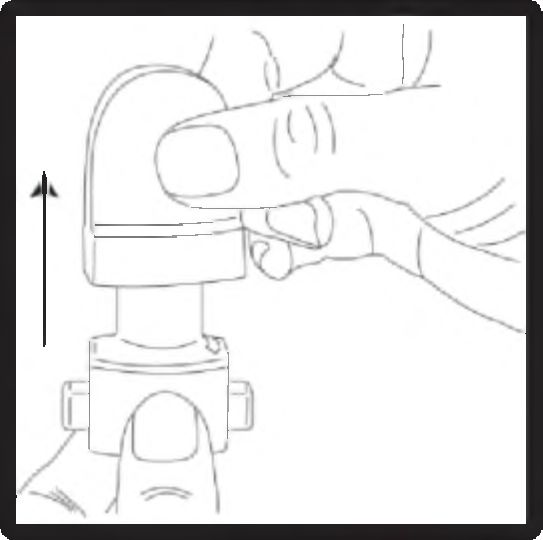

1. Kapağı çekip çıkarınız.

2. Kapsül bölmesini açınız.

İnhalerin tabanını sıkıca tutup, açmak için ağızlığı üzerinde yer alan ok işareti yönünde döndürünüz.